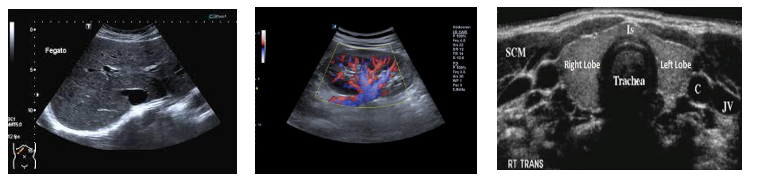

L’ecografia è una metodica diagnostica non invasiva che utilizzando ultrasuoni (onde sonore) emessi da particolari sonde appoggiate sulla pelle del paziente, consente di visualizzare organi, ghiandole, vasi sanguigni, strutture sottocutanee ed anche strutture muscolari e tendinee in numerose parti del corpo.

L 'ecografia è ampiamente utilizzata per lo studio di:

• collo (tiroide, linfonodi, gh salivari)

• addome (fegato, reni, milza, pancreas)

• pelvi (vescica, utero, ovaie, prostata)

• dell’apparato muscolare (muscoli, tendini, legamenti)

• tessuti molli , cute e sottocute.

• Apparato genitale maschile ( epididimo,didimo, sacco scrotale)

• Anca del neonato (screening neonatale)